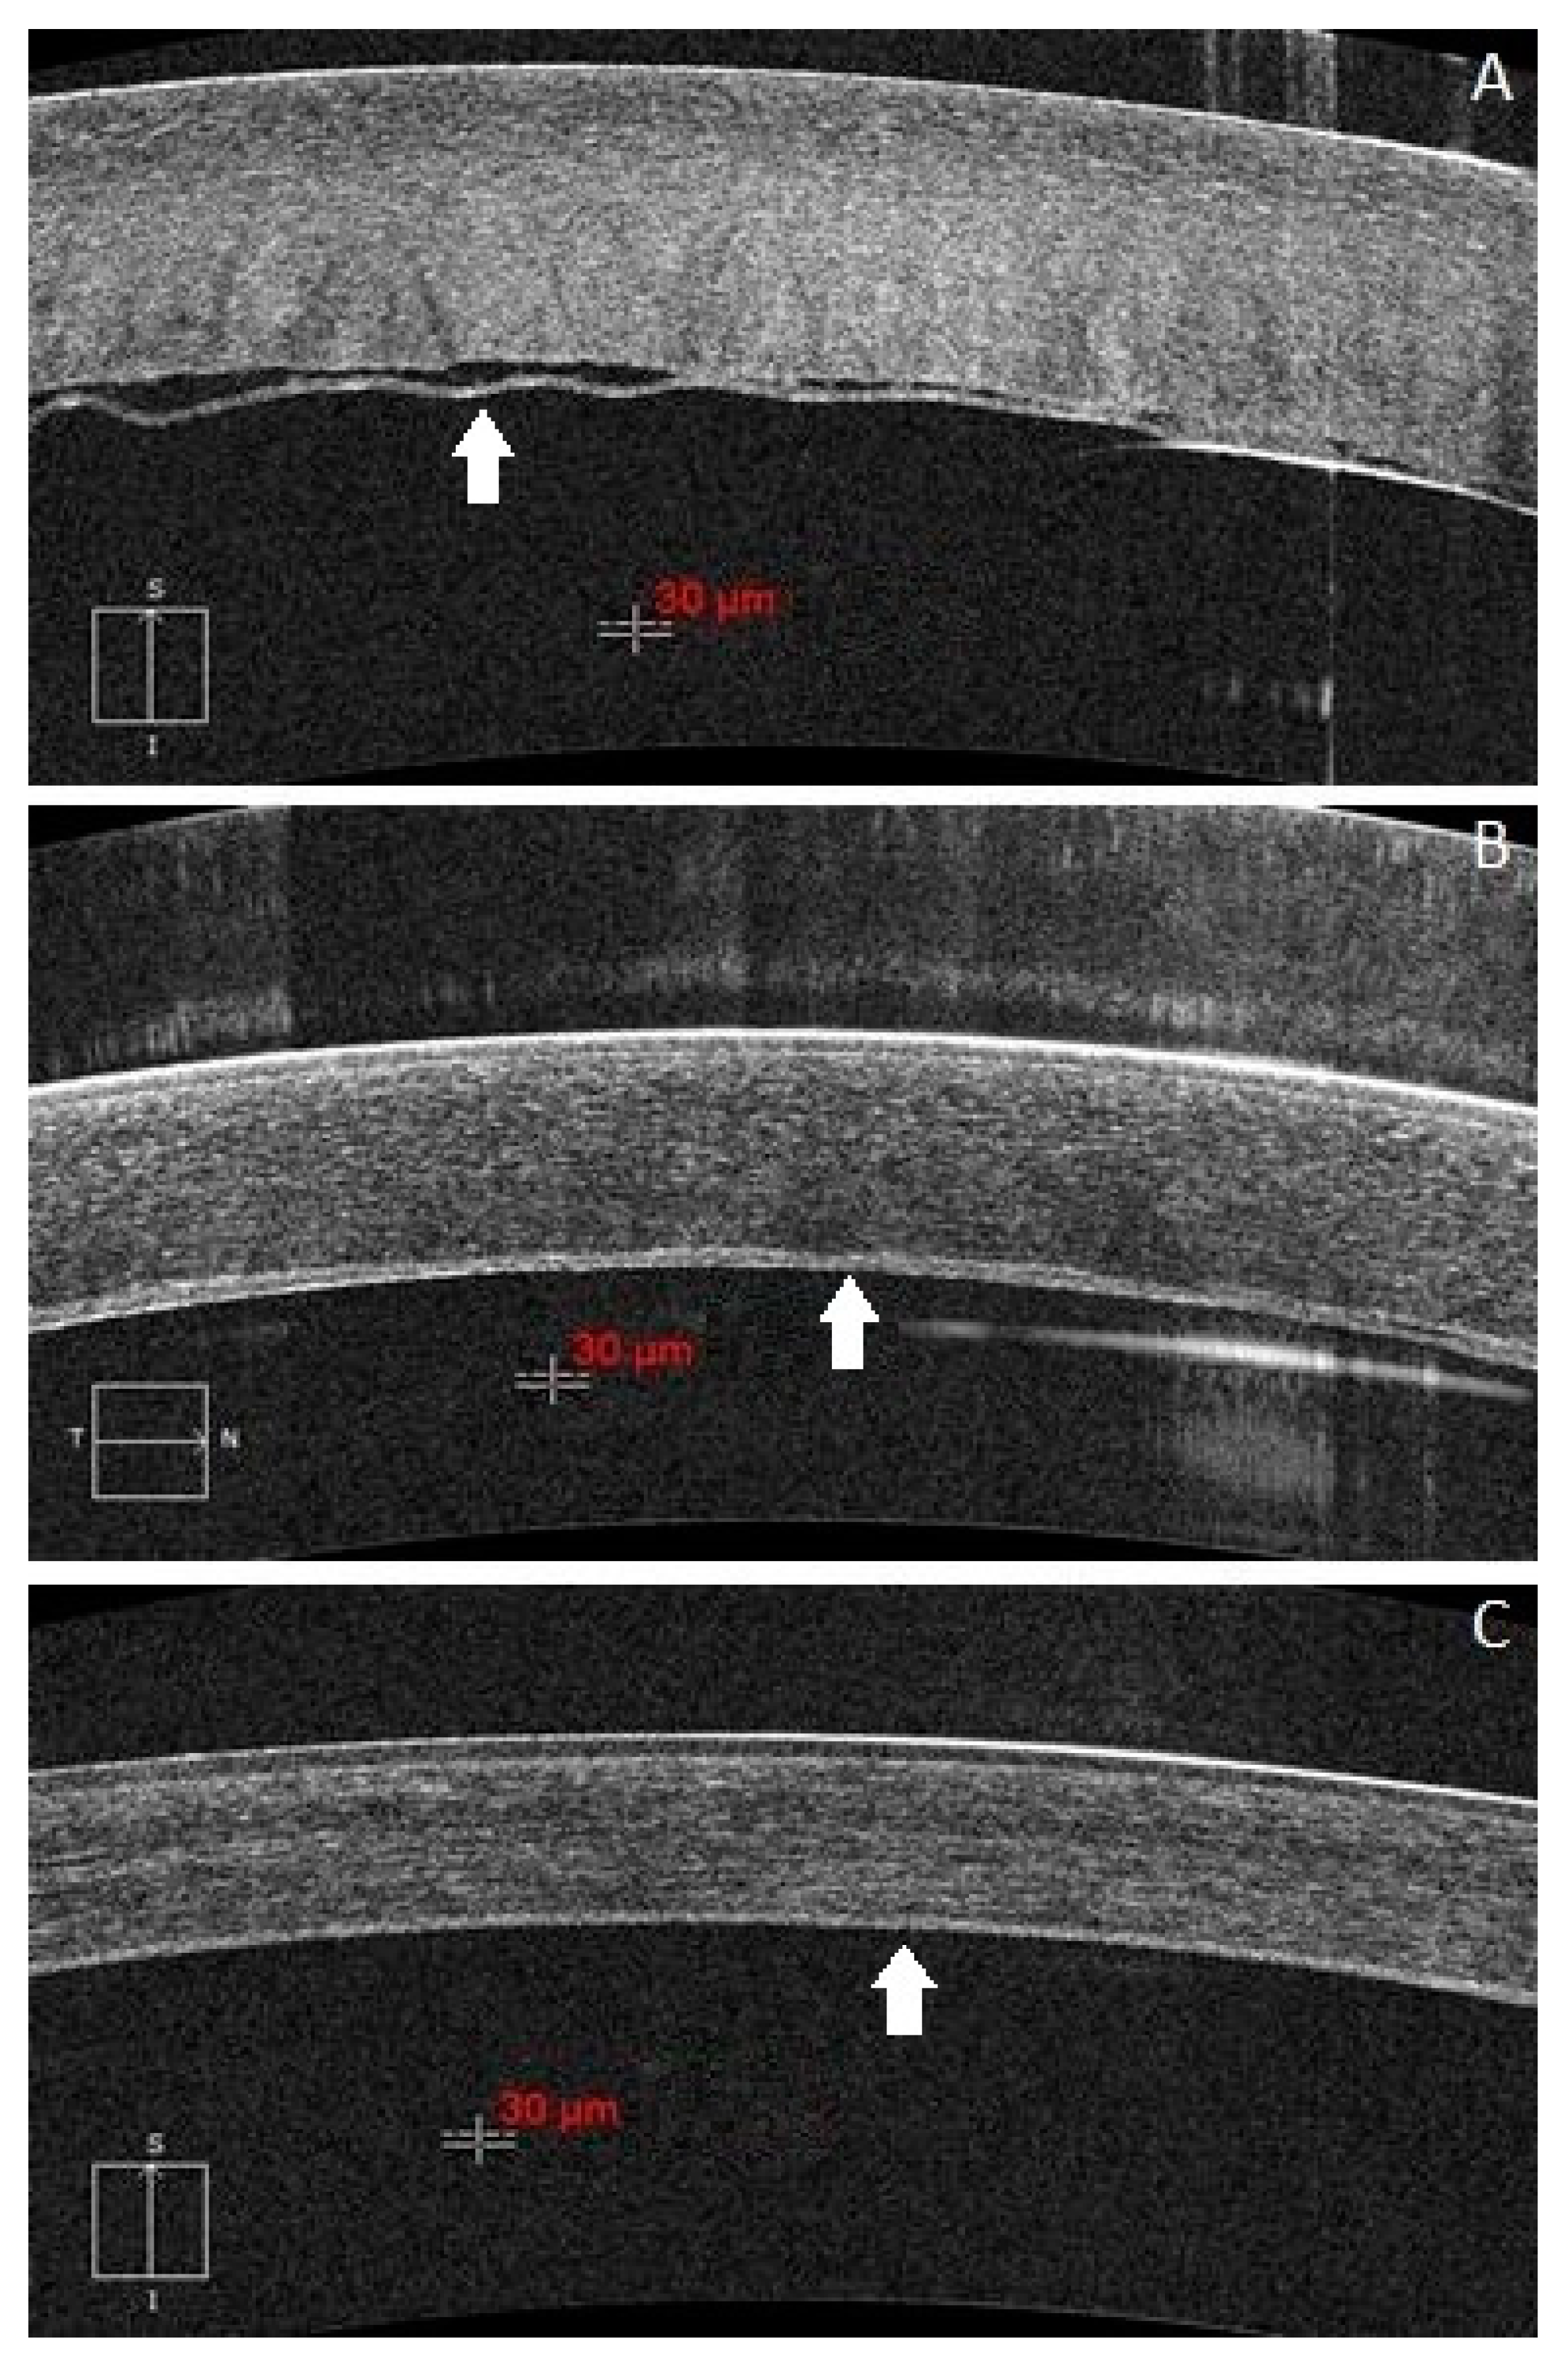

2. Subjects

3. Image Acquisition and Processing